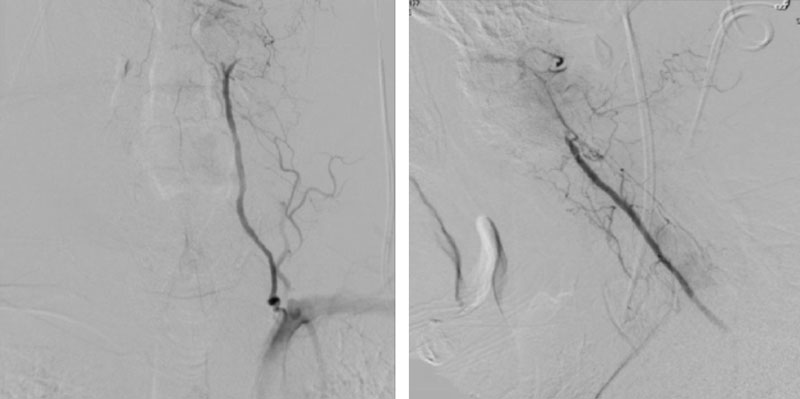

During neutral positioning, the vertebrobasilar circulation fills briskly from the Right Vertebral Artery. (Figure 4)

On rotation to the left, the patient experienced mild symptoms, however no significant Vertebral Artery or basilar reduction in flow was observed. On rotation to the right, the patient experiences slightly more moderate symptoms, however no significant Vertebral Artery or vascular reduction flow was observed. On hyper extension of approximately 10-15 degrees, passively performed by the patient until symptoms are reproduced, angiogram demonstrates complete occlusion of the right Vertebral Artery at approximately the C2-C1 level. (Figure 5)